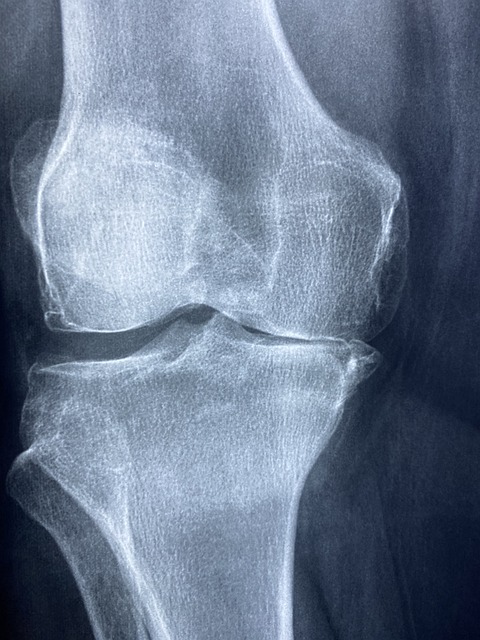

c. 영상 검사:

- 엑스레이: 엑스레이는 뼈와 관절 공간을 시각화하는 데 일반적으로 사용됩니다. 퇴행성 관절염은 종종 엑스레이에 관절 공간이 좁아지고, 골밀도가 변화하는 등 특징적인 변화를 보입니다.